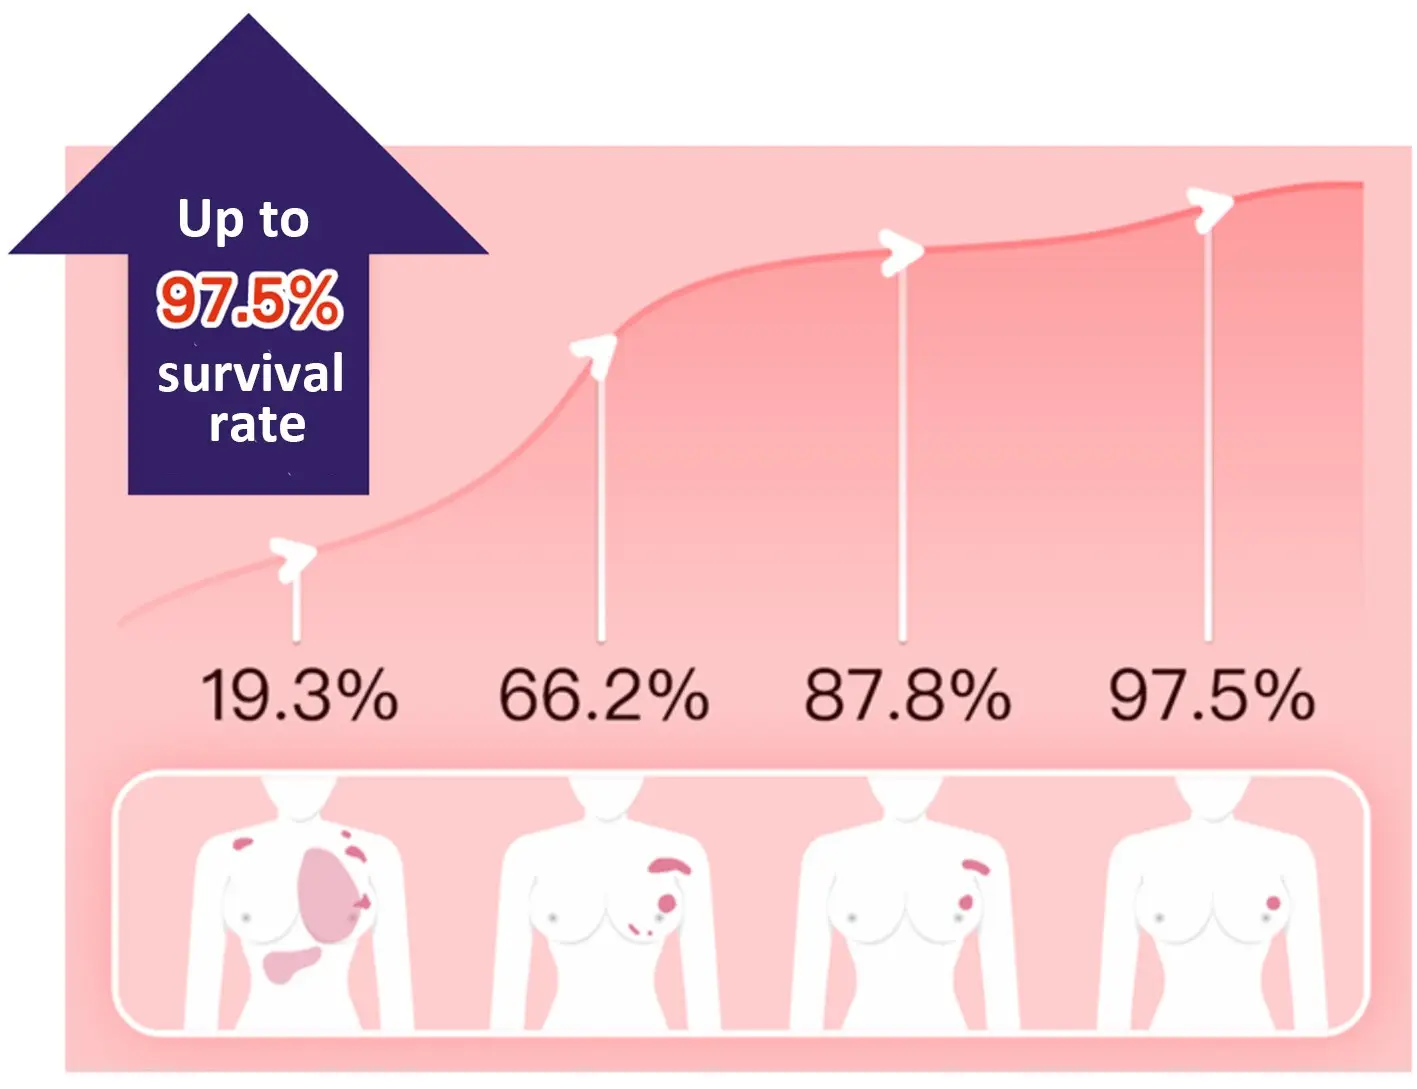

With advances in treatment methods, the five-year survival rate for early-stage cancer can reach 80-90%. However, the average detection rate for early-stage cancer is only 20-30%. The main reason is that early-stage cancer (lesions below 5mm) often has inconspicuous symptoms, and neither ultrasound nor X-ray examinations are very effective in detecting abnormal cells.